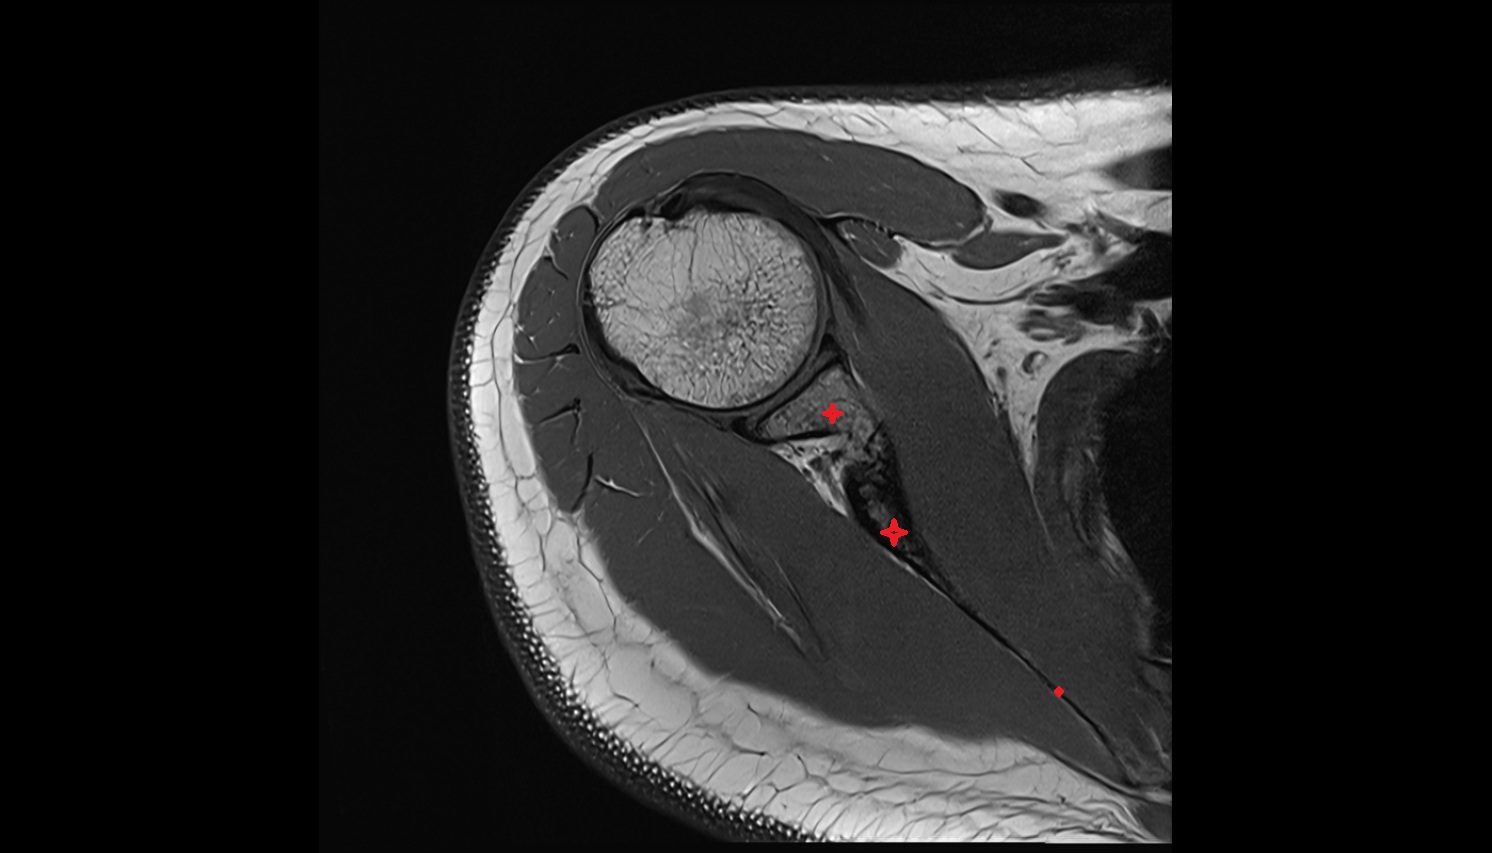

- Shoulder joint (glenohumeral joint)

- Glenoid labrum

- Glenohumeral joint capsule

- Supraspinatus tendon

- Infraspinatus tendon

- Subscapularis tendon

- Long head of biceps tendon

- Short head of the biceps brachii tendon